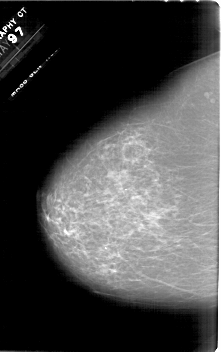

A_1618_1.LEFT_CC

LEFT_CC LINES 6676 PIXELS_PER_LINE 4186 BITS_PER_PIXEL 12 RESOLUTION 43.5 NON_OVERLAY